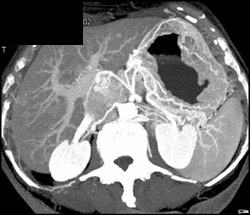

Normal Hepatic Artery